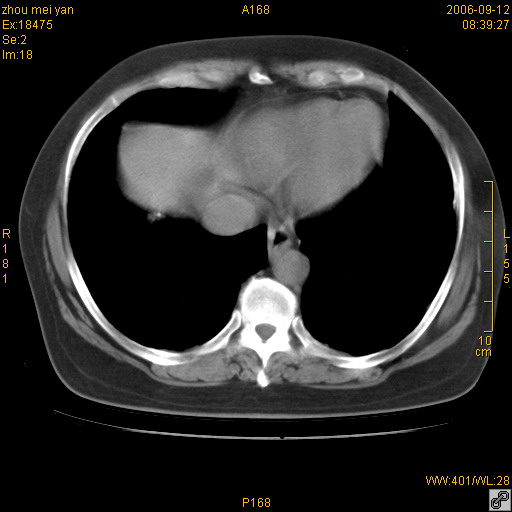

患者、女、55岁。因心率失常住院检查ct发现胸部多发结节。腹部b超肝、胆、胰、脾、肾、子宫附件未见异常。无结核病史,无粉尘接触史。请大家来会诊。谢谢!

病变位于胸膜,多发结节,边界清楚,内见小结节状钙化。其它未见异常。

双侧胸膜多发结节,形态不规则,边缘较清楚,每一个结节中心似乎都有钙化点的特征,与胸膜广基相切。临床无结核病史,无粉尘接触史。

影像表现十分有特点:双侧肋胸膜及膈胸膜广泛散在分布大小在2至6mm左右,较大病灶中心可见钙化。

考虑恶性胸膜间皮瘤可能性大,病灶位于胸膜,以宽基地与胸膜相连,呈结节样改变,部分病灶内可见点状钙化影。请各位老师多多指导!

双侧肋胸膜及膈胸膜广泛散在分布大小不等结节影,较大病灶中心可见钙化。